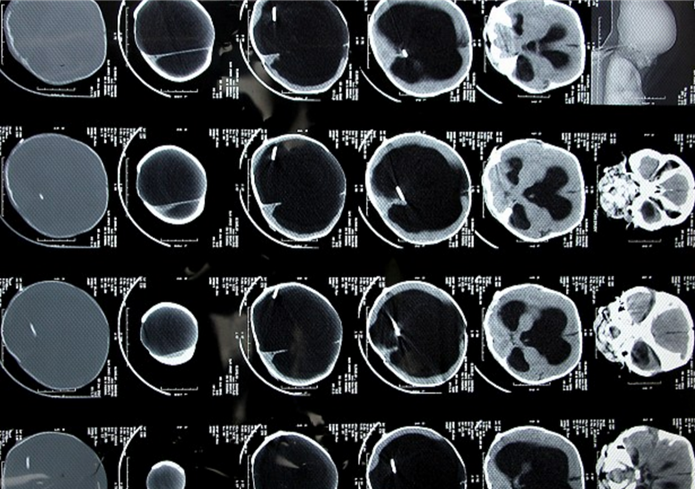

帕拉巴哈和丈夫?yàn)榱酥委熈_亞爾的疾病已經(jīng)花費(fèi)了2000英鎊(約1.75萬(wàn)元人民幣),但目前看來(lái),羅亞爾的病情并沒(méi)有明顯好轉(zhuǎn)。醫(yī)生目前的治療方案是通過(guò)分流將羅亞爾腦中的積液引入血液,以減輕羅亞爾腦部壓力。

帕拉巴哈的丈夫拉金德拉是一名勞工,每月的收入只有50英鎊(約438元人民幣)??紤]到羅亞爾的病情以及夫婦二人的經(jīng)濟(jì)狀況,醫(yī)院本周免費(fèi)為羅亞爾進(jìn)行了新一輪手術(shù)。該醫(yī)院神經(jīng)外科的副主任錢(qián)德拉表示,羅亞爾之前在別家醫(yī)院植入的分流器已經(jīng)停止工作,在這次的手術(shù)中,醫(yī)生在羅亞爾腦部的另一側(cè)植入了新的分流器,目前,羅亞爾的情況正在一天天好轉(zhuǎn)。

錢(qián)德拉說(shuō):“這種疾病的死亡率極高,患者的身體和腦部發(fā)育都異于常人。如果沒(méi)有及早發(fā)現(xiàn)、及早治療,嬰兒死亡的可能性將更大?!?/p>